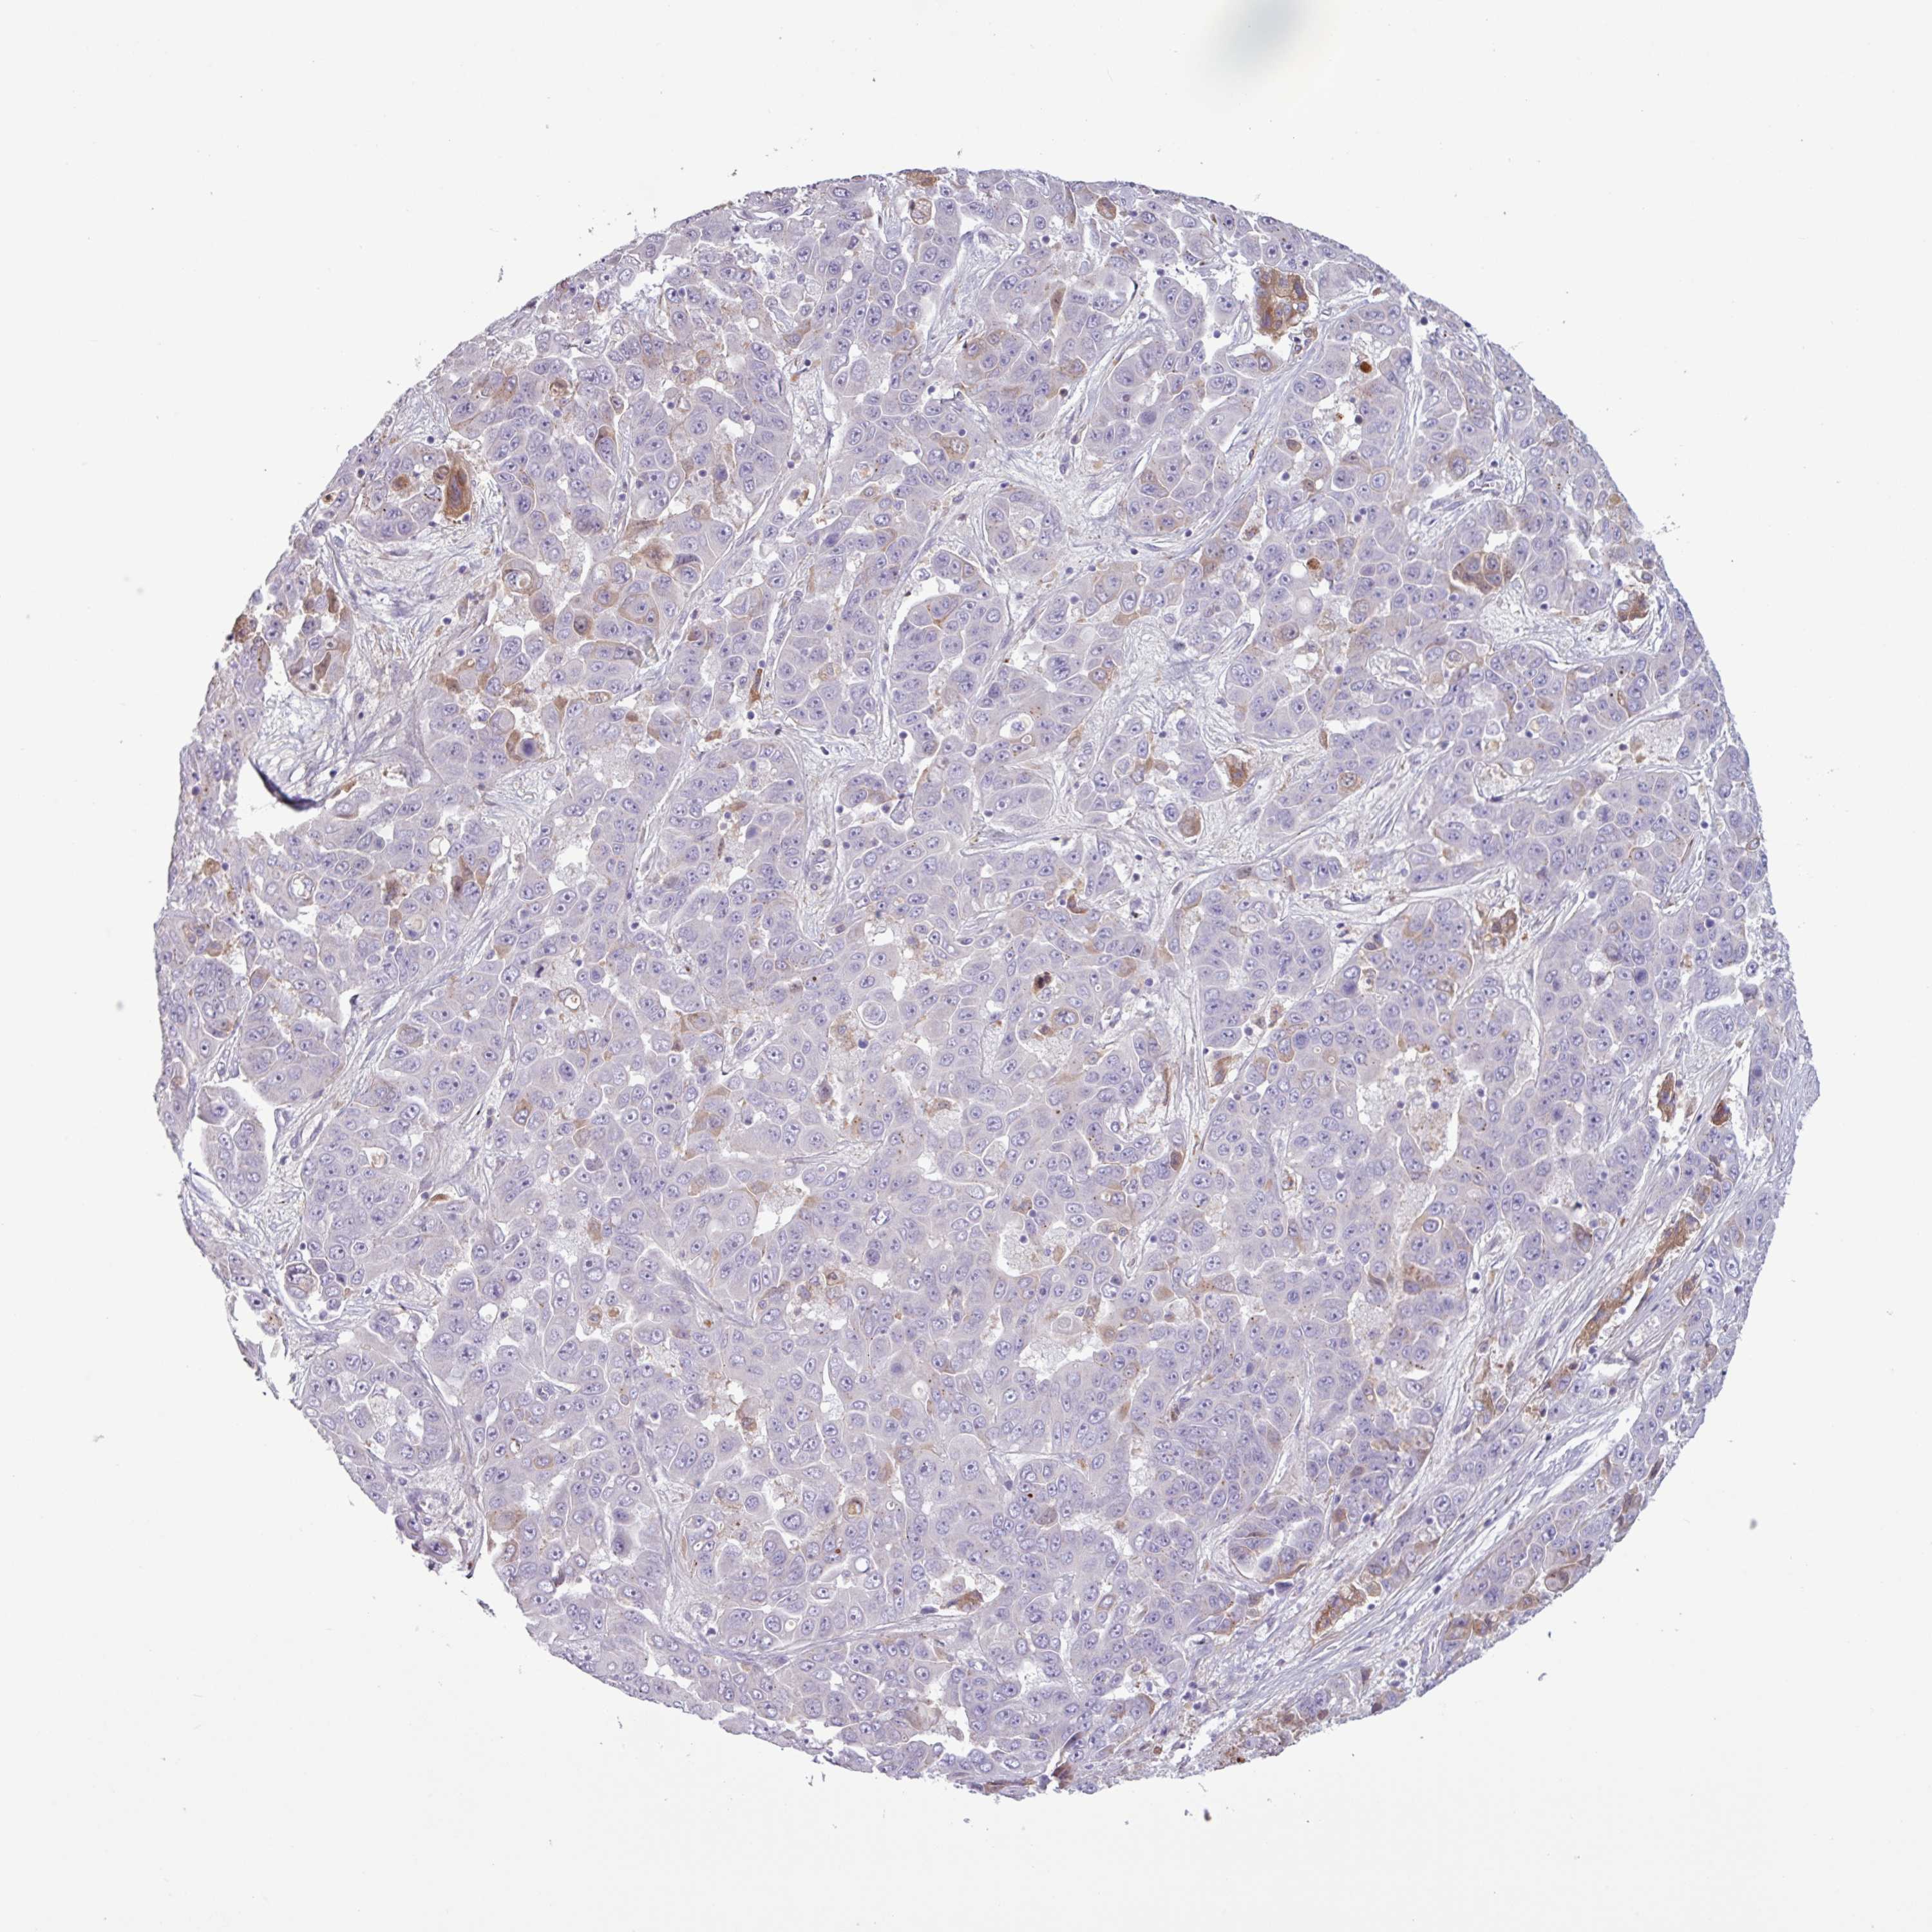

LIVER CANCER - Protein expressioni

A mouse-over function shows sample information and annotation data. Click on an image to view it in a full screen mode. Samples can be filtered based on level of antibody staining by selecting one or several of the following categories: high, medium, low and not detected. The assay and annotation is described here.

Note that samples used for immunohistochemistry by the Human Protein Atlas do not correspond to samples in the TCGA dataset.

Antibody stainingi

Antibody staining in the annotated cell types in the current human tissue is reported as not detected, low, medium, or high, based on conventional immunohistochemistry profiling in selected tissues. This score is based on the combination of the staining intensity and fraction of stained cells.

Each image is clickable and will lead to virtual microscopy that enables deeper exploration of all samples and also displays staining intensity scores, fraction scores and subcellular localization as well as patient and tissue information for each sample.

HPA046356

HPA048287

HPA050103

CAB009811

CAB032603

Staining

High

Medium

Low

Not detected

Intensity

Strong

Moderate

Weak

Negative

Quantity

>75%

75%-25%

<25%

None

Location

Nuclear

Cytoplasmic/membranous

Cytoplasmic/membranous,nuclear

Cholangiocarcinoma

Carcinoma, Hepatocellular, NOS